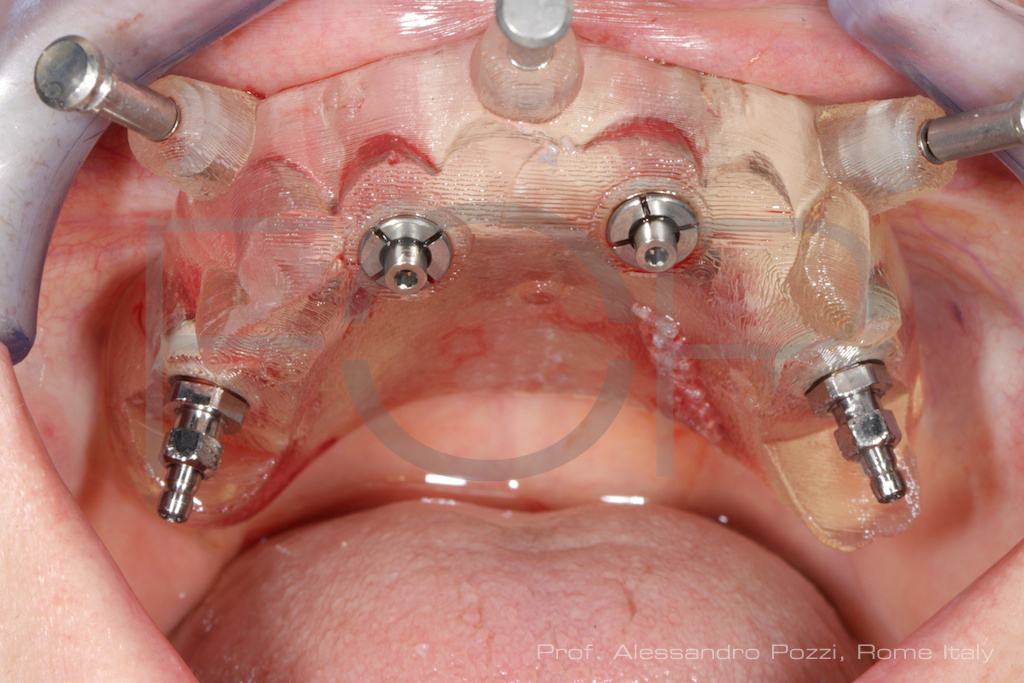

Quando os critérios de estabilidade primária são alcançados, é possível realizar a carga imediata, com a instalação de uma prótese fixa provisória em até 24 ou 72 horas após a cirurgia.

Essa etapa proporciona benefícios funcionais e psicológicos ao paciente, além de facilitar a adaptação ao novo esquema oclusal.

Fixação da Prótese Provisória